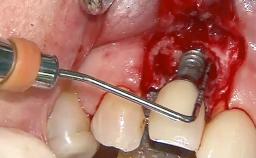

Open-Flap Debridement for the Management of Peri-Implant Mucositis Associated with Excess Cement

A 79-year-old female patient was referred to the Department of Periodontology of the University of Bern, Switzerland by her private dentist in May 2019. She had been rehabilitated in May 2005 with two tissue-level implants (Institut Straumann AG, Basel Switzerland) at sites 13 and 15, supporting a three-unit cemented fixed dental prosthesis (FDP). The metal-ceramic FDP had been cemented permanently with a glass-ionomer cement (Ketac Cem; 3M ESPE, Seefeld, Germany). Implant 13 had been diagnosed with peri-implant mucositis by the referring dentist in the course of regular supportive therapy. The patient was in good general health, did not smoke, and exhibited good self-performed plaque control.